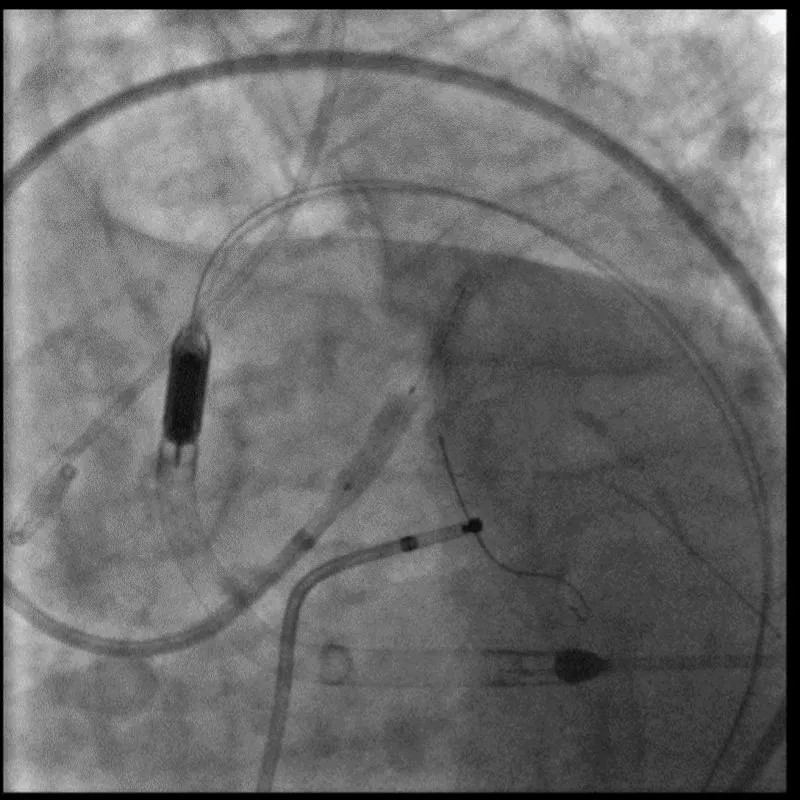

With the support of deep sedation, an angio-guided right femoral access was obtained, and a 12F introducer was advanced. We crossed the aortic valve with an Amplatzer left 1 catheter with a 0.035” wire and exchanged the wire with an extra-stiff Safari. We performed aortic Valvuloplasty with a Nucleus balloon 18 x 40 mm. (Figure 7) Then, we exchanged the wire and advanced an IMPELLA CP device, starting a protected PCI on LM. (Figure 8) An EBU 4.0 catheter was advanced, the stenosis was crossed on the Left Main (LM) and mid-Left Anterior Descending artery (LAD) using a BMW guide wire, and with the aid of a microcatheter a 0.014” Rotawire was positioned, followed by rotational atherectomy using a 1.5 mm burr on LM and mid LAD, (Figure 9) and a 2.0 mm burr on LM alone (Figure 10). This was followed by predilation with a 2.5 x 20 mm SC balloon and the implantation of a 2.5 x 32 mm Synergy drug-eluting stent (Figure 11). Then, the Left Main was predilated with a 3.5 x 12 mm NC balloon, and a 4.0 x 15 mm Xience Sierra drug-eluting stent was implanted and post-dilated with a 4.5 x 8 mm SC balloon (Figure 12). Immediate angiographic control confirmed a successful result. Then we removed the IMPELLA CP device and advanced a 14F e-sheath Edwards on the right femoral artery, crossed the aortic valve with a Safari extra-stiff wire, and performed a Sapien 3 23 mm valve implantation with a good angiographic result (Figure 13). Post-procedural echocardiographic and angiographic assessment confirmed the valve was correctly positioned, with no significant gradient and a minimal residual leak. The procedure was uneventful, and the patient was discharged on the fourth day with triple therapy: Aspirin 100 mg once daily, Clopidogrel 75 mg once daily, and Apixaban 2.5 mg twice daily. At the quarterly follow-up, the patient reported hospitalization for anemia, requiring a transfusion of 3 units of packed red blood cells. Endoscopic exams were negative, and hypochromic, normocytic anemia persisted. Given the patient’s CHA2D2-VASc score of 5, HAS-BLED score of 4, and recent dual Drug-Eluting Stent (DES) implantation, she was admitted for left atrial appendage percutaneous closure. Before this procedure, a repeat coronary angiography showed good results in the previously implanted stents (Figure 14). Subsequently, through a right femoral percutaneous approach using a 12F introducer, a 22 mm Amulet device was positioned for left atrial appendage closure (Figure 15). The procedure was completed without complications. At the 4-year follow-up, the patient presented in good hemodynamic status, with an echocardiographic ejection fraction of 55%. She continued on clopidogrel 75 mg once daily therapy.

Download Image

Figure 8: Impella CP Device.